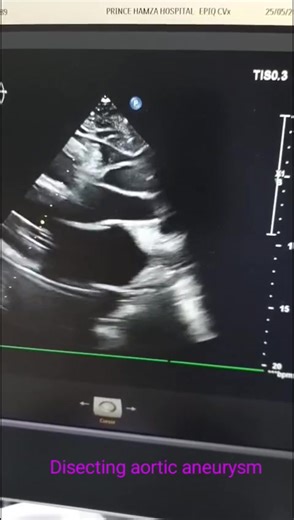

Aortic Dissection Treatment | Cleveland Clinic